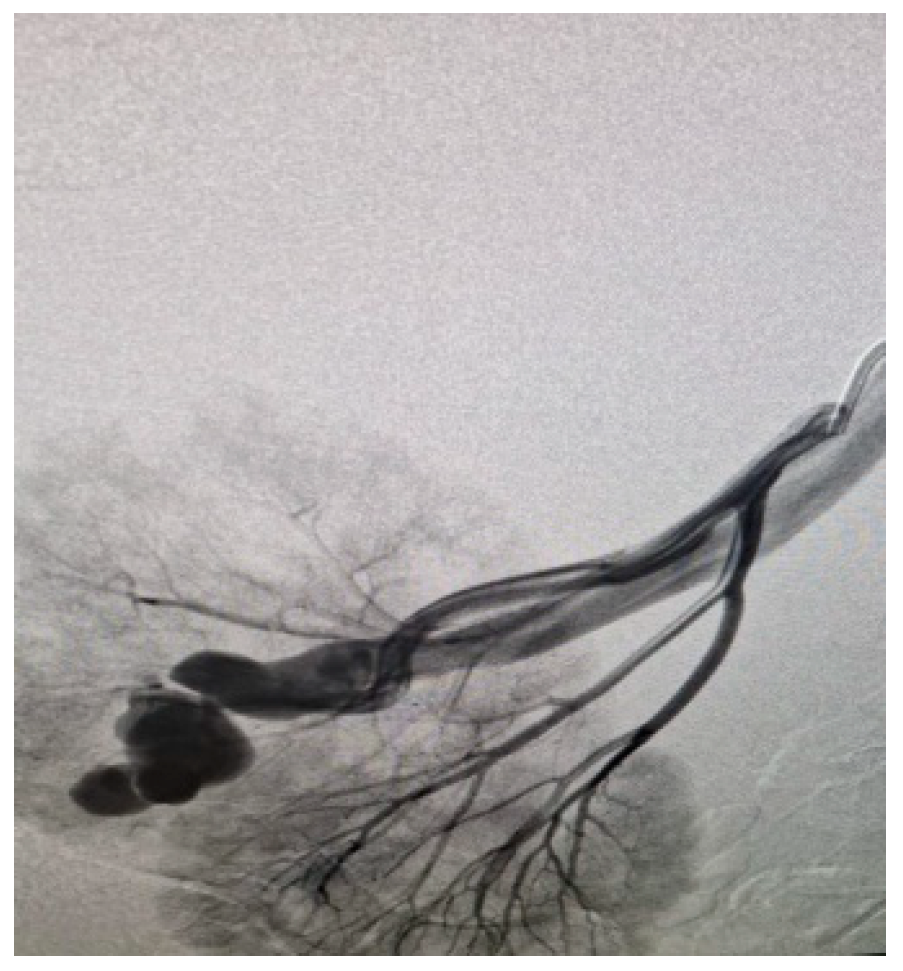

Appendix A.1. Clinical Case 1: Right Renal Visceral Arteriovenous Malformation